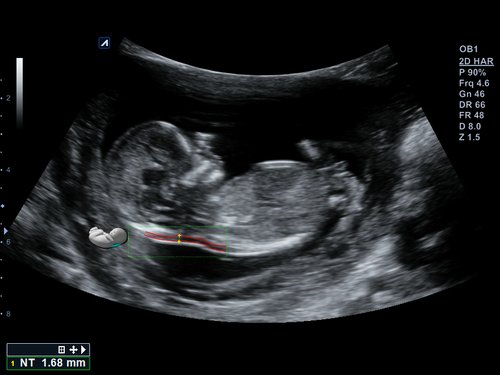

• Volume Master, Volume Advance, Live HQ, Auto NT (Geburtshilfe)

• EV3-10T (3-10 MHz) für Ultraschalluntersuchungen in Bereichen Geburtshilfe, Gynäkologie, fetales Echo, Urologie

• C1-6CT (1-6 MHz) für Ultraschalluntersuchungen in Bereichen Abdomen, Geburtshilfe, Gynäkologie, fetales Echo